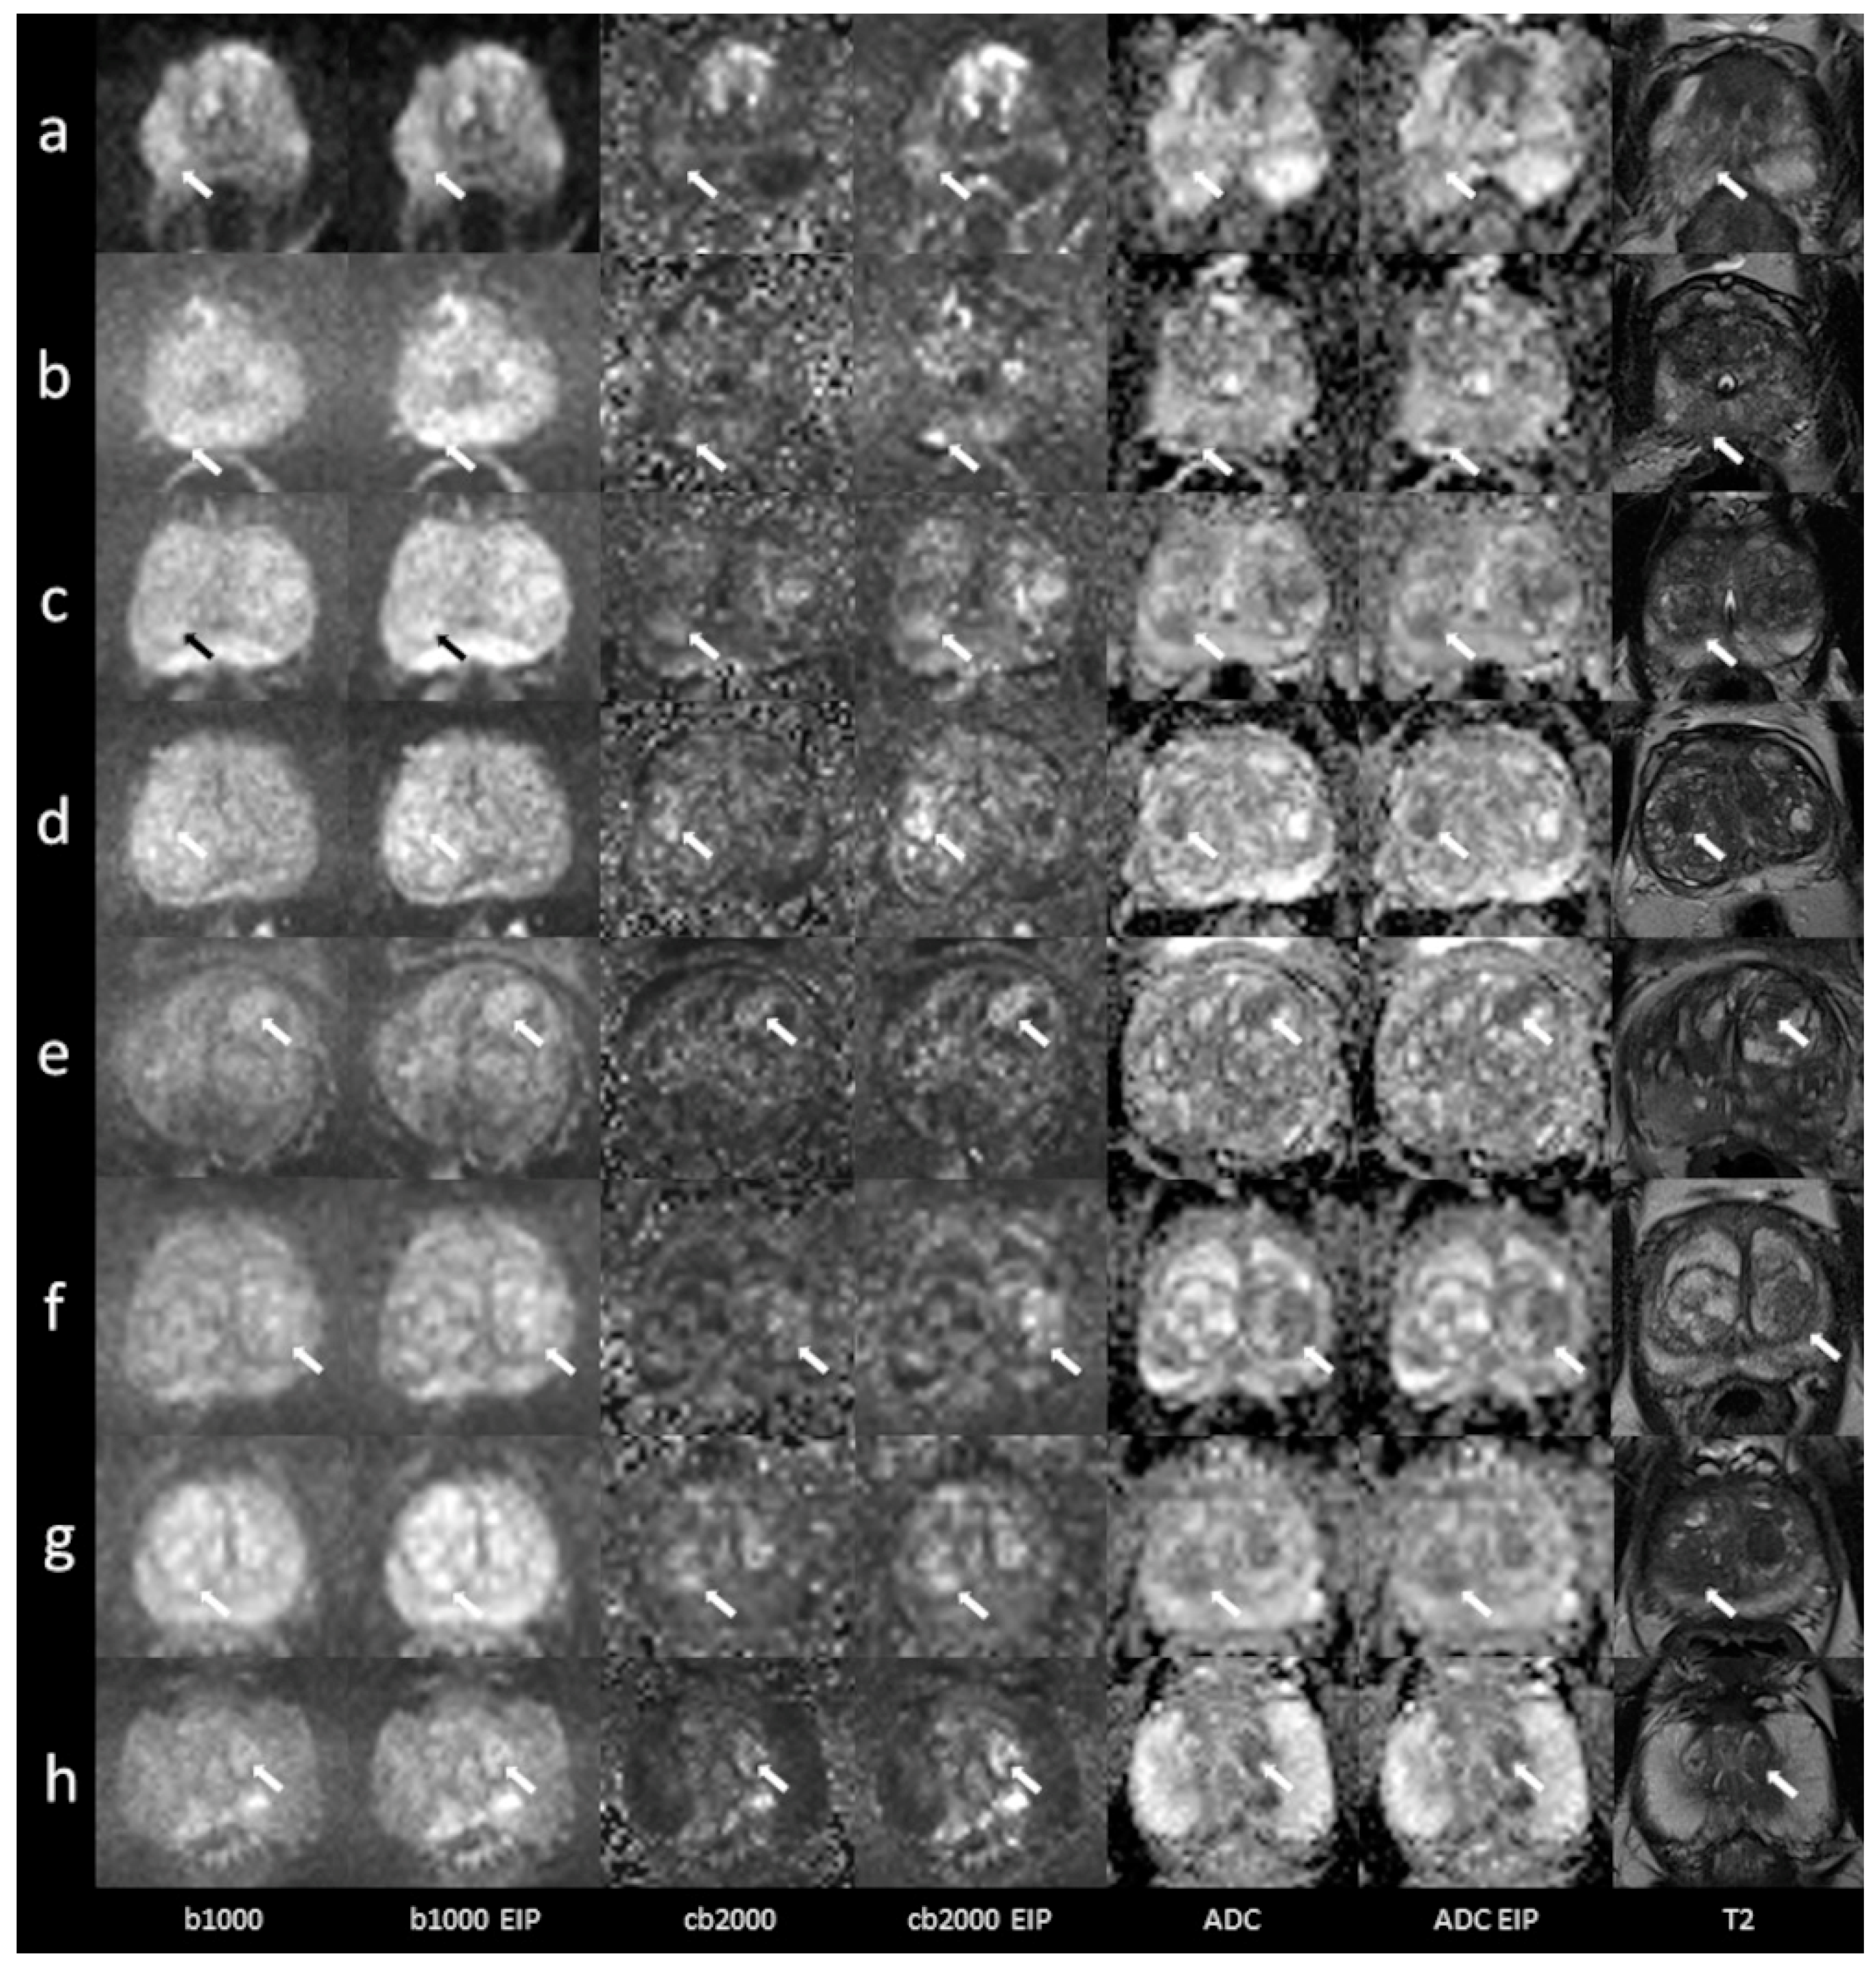

4.2.2. Peripheral Zone

4.2.3. Transition Zone